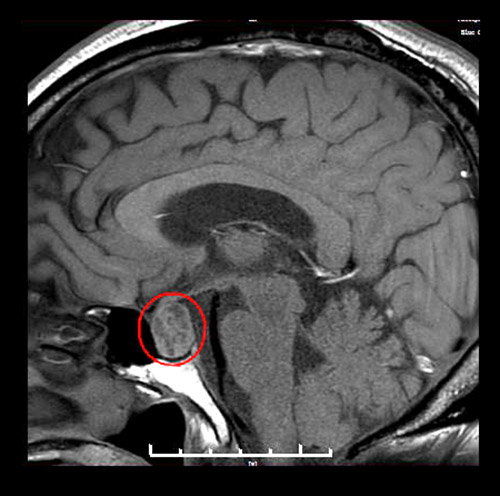

▲術前MR影像:垂體大腺瘤,超蝶鞍生長

神經外科執(zhí)行主任潘仁龍詳細了解了患者的病情,為其完善各項檢查。鞍區(qū)MRI平掃+增強顯示,患者蝶鞍稍擴大,鞍底骨質下陷;鞍內垂體上緣膨隆,腺垂體中央見一枚類橢圓形異常信號,直徑約1.8*1.4厘米。綜合各項檢查結合臨床,王老伯確診為垂體大腺瘤(1~3cm的叫做大腺瘤)。